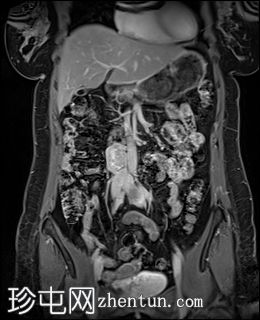

冠状位T1加权像

增强脂肪抑制像

右侧腹膜后可见一边界清晰的肿块,位于主动脉分叉上方。

病灶大小约为3.5 x 3.0 x 4.1 cm(前后径 x 横径 x 头尾径)。

T2加权像显示异质性高信号,DWI/ADC显示明显扩散受限,增强后明显强化。

对下腔静脉有轻微压迫,无直接侵犯或血栓形成的证据。

病灶旁可见两个小的、不规则的淋巴结,疑似转移。

影像学特征符合高血管性腹膜后病变的典型表现。

病变位于祖克坎德尔氏器,且具有明显的强化和扩散受限,强烈提示副神经节瘤。